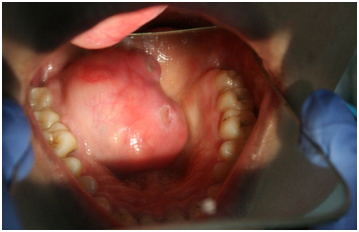

A 23 years old female presented with slow growing swelling of approximately 4 years of duration involving her hard and soft palate junction on the right side. The swelling was peanut size when she first observed. However as lesion had always been asymptomatic with no associated pain or paraesthesia the patient had neglected it. She only sought medical help when it started obstructing her speech and eating. The patient’s medical history was noncontributory. She had no known allergies and not undergone any surgeries of head and neck. Clinically the patient presented with typical ‘Hot potato in mouth’ speech. Inspection of the lesion revealed ulcerated dome shaped palatal swelling of size about 5x4 cms in the posterior part of hard palate right side extending on to the soft palatal junction crossing the midline. The overling mucosa was red and stretched and presented as a single mass without any nodules. The lesion was firm non tender and not blanching to pressure on palpation (Figure 1).

Figure 1 Preoperative view of growth with ulceration on the surface.